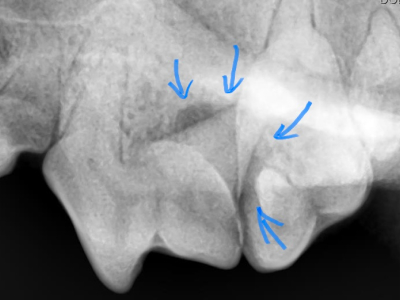

治療前X線

X線で確認するとやはり根っこの周りの骨が歯周病によりなくなっています。